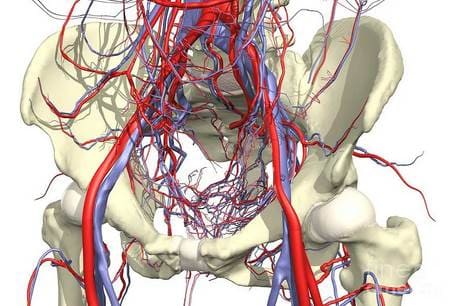

Tak więc stawy mają dość złożony system zaopatrzenia w krew, składający się z wielu cienkich naczyń włosowatych. Kiedy większość naczyń włosowatych zostaje zablokowana lub martwa, krew zaczyna płynąć przez te naczynia, które nie zostały uszkodzone. Prowadzi to do ich rozszerzenia i szybkiego zużycia z powodu ich przeciążenia. Ponadto takie zatkane naczynia krwionośne są bardziej wrażliwe na zmiany pogody. Boli tych, którzy są wrażliwi na pogodę.

Układ krążenia stawu jest układem złożonym.

Zdrowie stawów zależy bezpośrednio od ich

stanu.